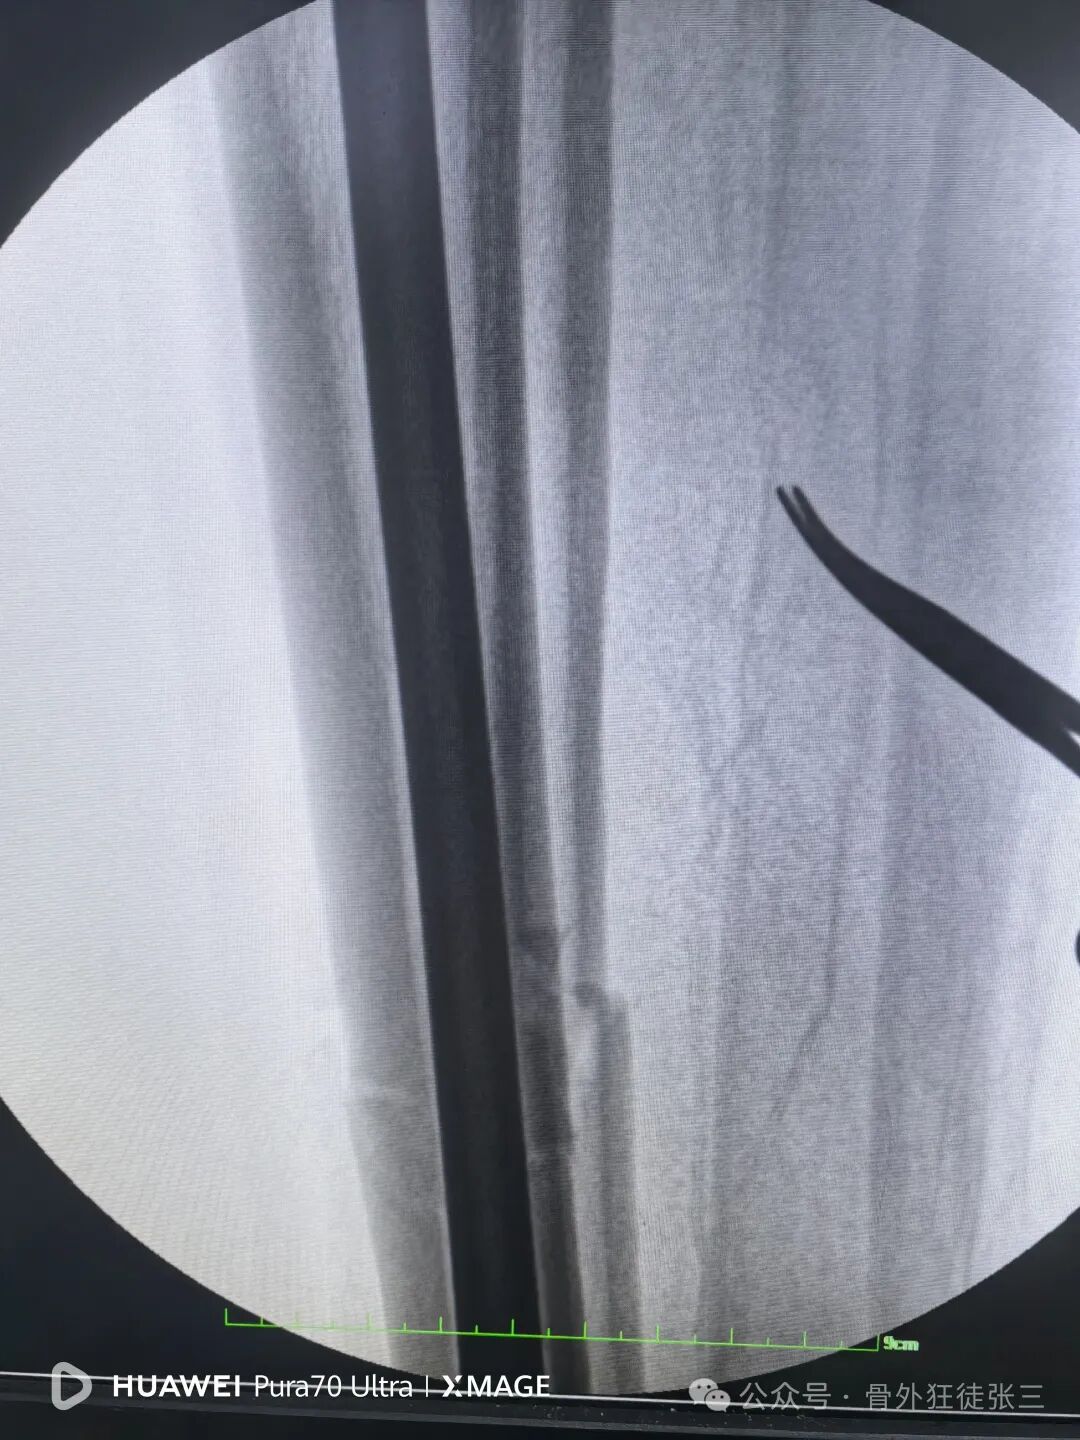

踝关节侧位钉子长度满意,居中

7,髓内钉本身就是复位工具,在此时依靠髓内钉+手法,几乎都能顺利复位。